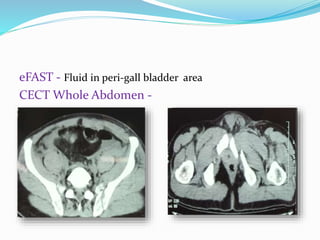

eFAST - Fluid in peri-gall bladder area

CECT Whole Abdomen -